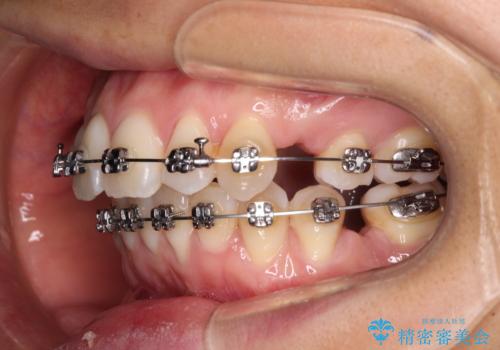

- 矯正装置

- メタルブラケット

- 治療期間

- 1年11ヶ月

非抜歯矯正ではデコボコを解消することでより口元が突出してしまうため、上下左右の小臼歯4本の抜歯を行い、ワイヤー装置による矯正治療を行うこととしました。